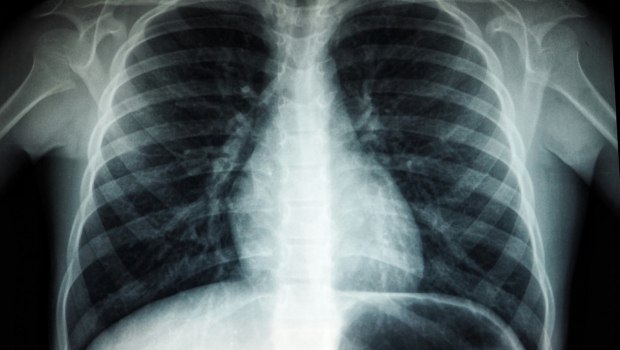

Ο καρκίνος του πνεύμονα παραδοσιακά συνδέεται με το κάπνισμα, όμως τα τελευταία χρόνια παρατηρείται αύξηση στα περιστατικά μεταξύ μη καπνιστών.

Σήμερα, το 10-25% των περιστατικών είναι άτομα που δεν έχουν καπνίσει ποτέ, με τη συντριπτική πλειονότητα να αφορά το αδενοκαρκίνωμα — μια μορφή καρκίνου που συνδέεται με την ατμοσφαιρική ρύπανση.